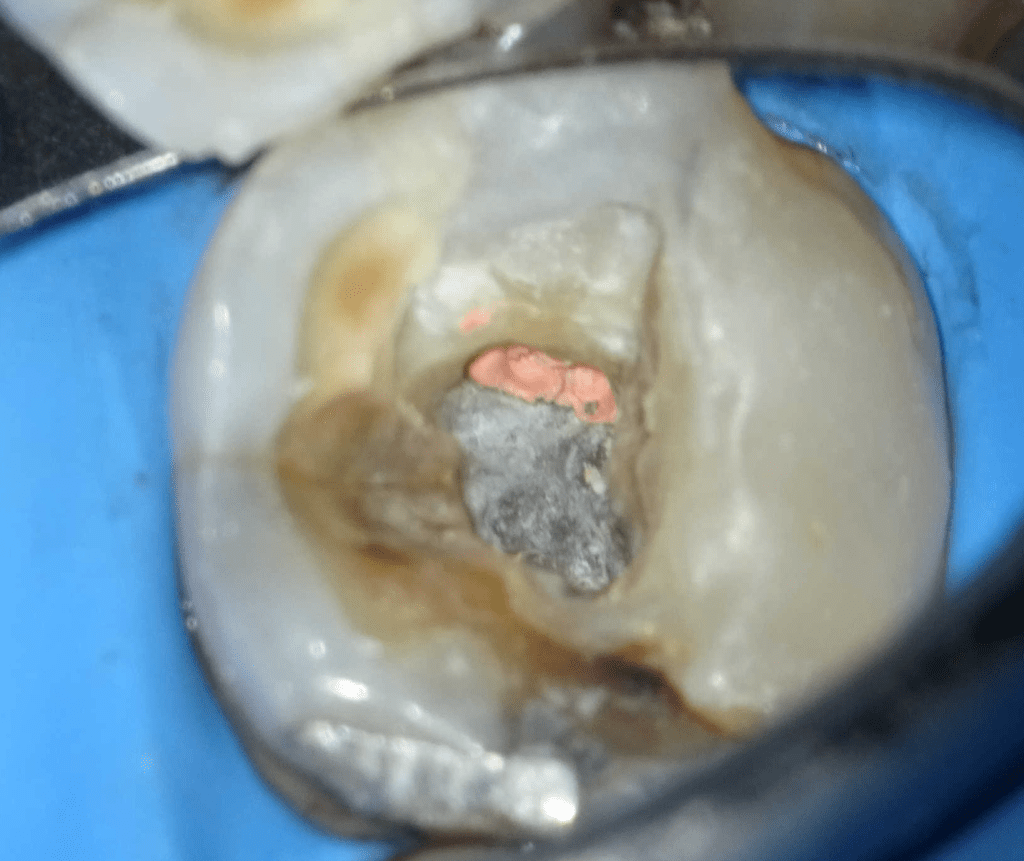

Pulpotomía biodentine + reco preendio